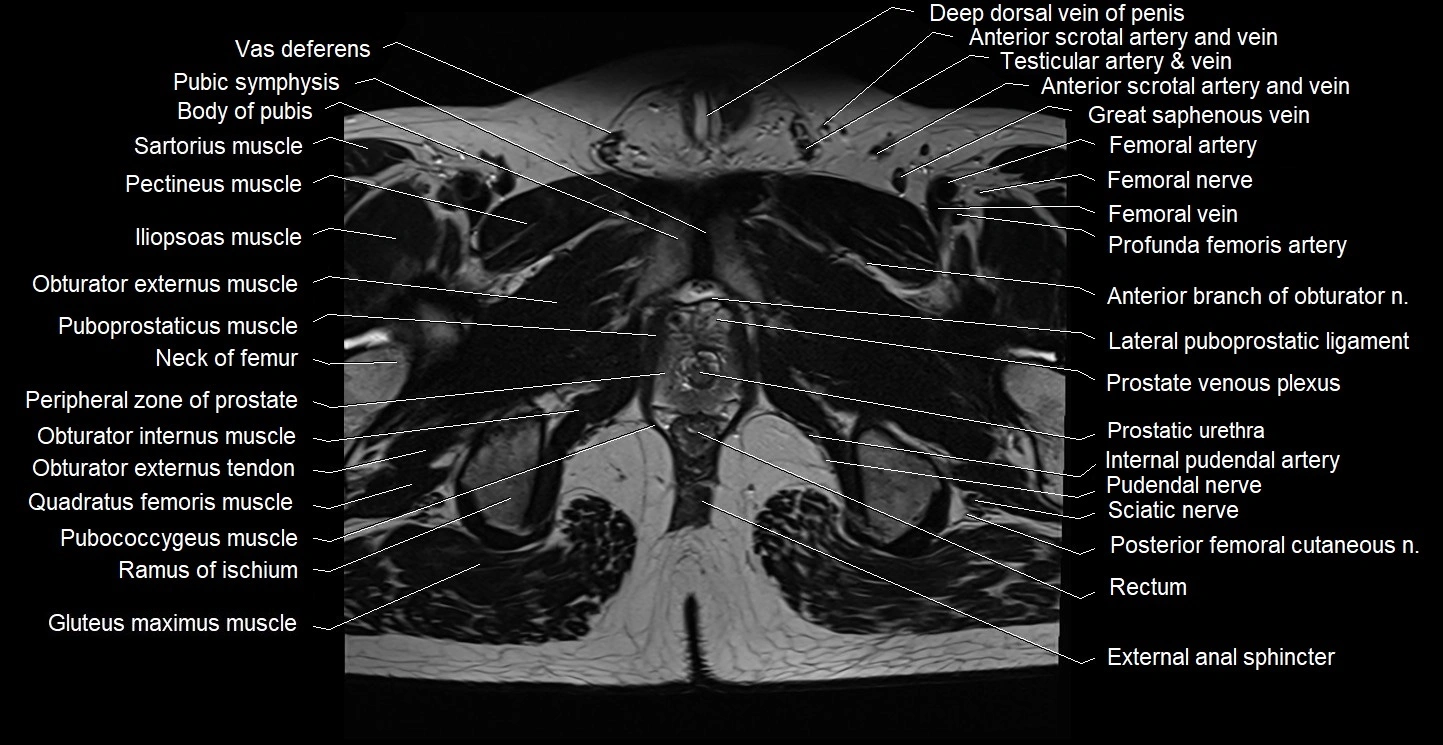

- Body of pubis

- Neck of femur

- Peripheral zone of prostate

- Prostatic urethra

- Pubic symphysis

- Pubococcygeus muscle

- Puboprostatic ligament

- Puboprostaticus muscle

- Pudendal nerve

- Rectum